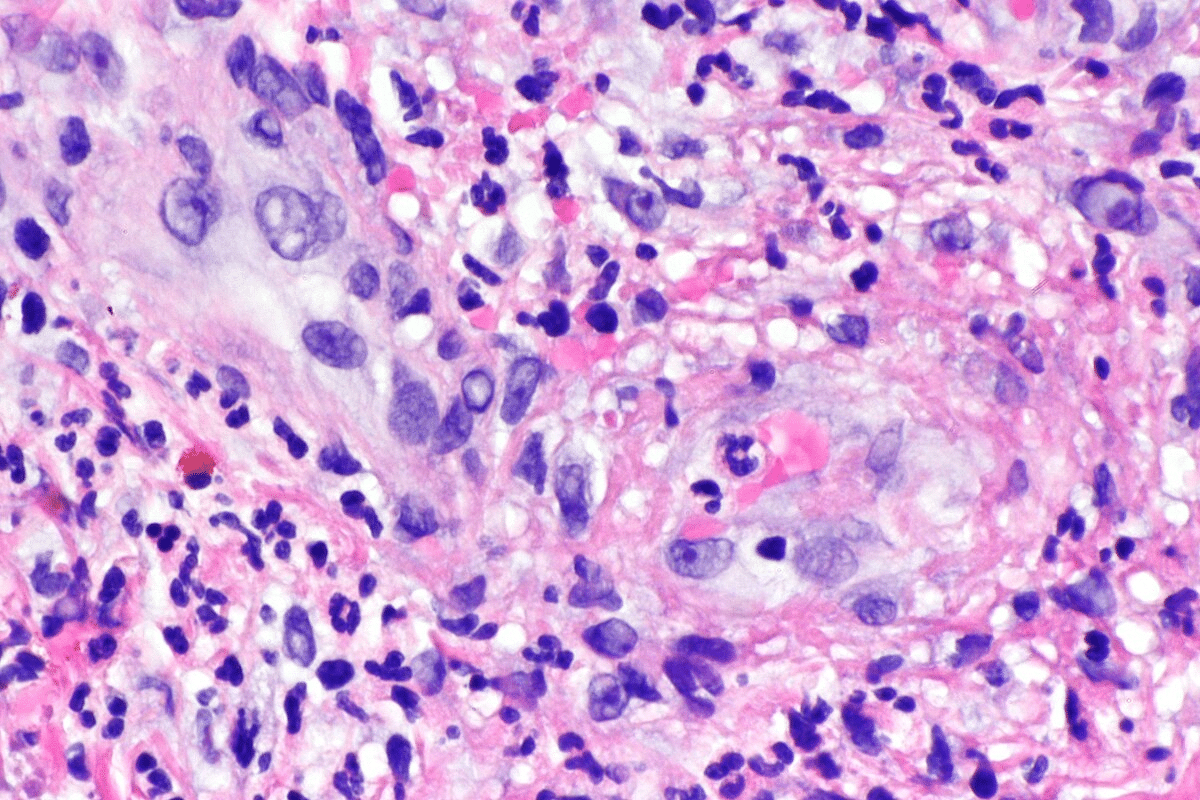

Histopathological Findings

Looking at biopsy samples under a microscope shows signs of vasculitis. These include inflammation, damage, and sometimes granulomas. These signs help confirm the diagnosis and pinpoint the type of vasculitis.

When Biopsy Is Necessary

Biopsy is needed when the diagnosis is unclear or the symptoms are unusual. It’s also key for tracking how the disease is doing and how well it’s responding to treatment. Sometimes, it’s used to rule out other diseases that might look like vasculitis.